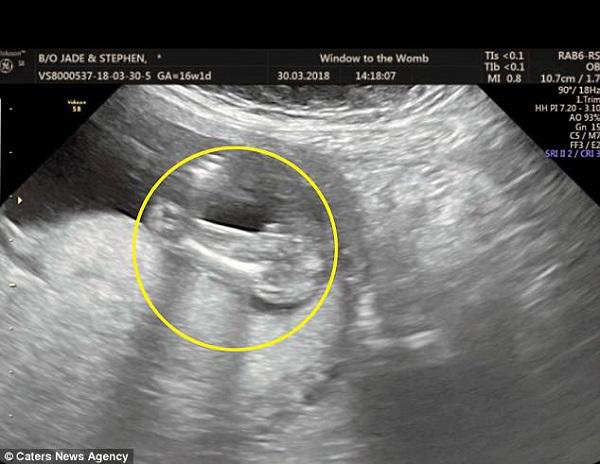

Trong lần khám gần nhất khi chị mang thai được 16 tuần, các bác sĩ siêu âm cho chị Jade và chẩn đoán rằng chị đang mang thai một bé gái, chuyện sẽ chẳng có gì đáng nói cho đến khi chị xem lại hình ảnh siêu âm con sau khi rời phòng khám. Chị Jade xem lại bức ảnh rất nhiều lần và nhận thấy có điều bất ổn với giới tính của bé, khi chồng chị nhìn vào bức ảnh cũng phải thốt lên rằng: “Em chắc đây là một bé gái chứ?”

Vô cùng sốt sắng khi muốn biết giới tính thật của con, ngay lập tức, Jade đăng tải bức ảnh chụp lại hình siêu âm lên nhóm tâm sự bà bầu trên Facebook, chia sẻ về việc chị được chẩn đoán mang thai bé gái và hỏi ý kiến mọi người về giới tính của em bé sau khi xem ảnh. Bà mẹ một con đã hoàn toàn ngạc nhiên khi trên bài đăng của chị tràn ngập những bình luận cho rằng em bé có hình hài thật kỳ lạ và trông giống như chiếc…dương vật khổng lồ.

Chị và chồng không hề nhận ra hình hài của con trông giống hệt dương vật cho tới khi chia sẻ bức ảnh lên mạng xã hội và hỏi ý kiến của các mẹ bầu khác.

“Tôi thực sự không nhận thấy cho tới khi mọi người đều nói rằng trông con tôi thật đáng yêu, họ nói rằng tôi có một em bé mang hình hài chiếc dương vật khổng lồ. Chuyện này thật đáng kinh ngạc, tôi đã bị sốc nhưng cũng thật hài hước và đáng yêu.”, chị Jade chia sẻ.

Mọi người đùi vui rằng chị có một cậu bé mang hình hài chiếc dương vật khổng lồ vô cùng hài hước.